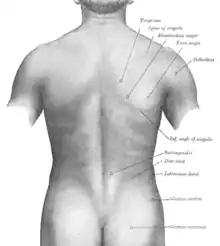

Dos

Dos humain

Le dos humain se compose de sept vertèbres cervicales, douze vertèbres thoraciques (ou dorsales), cinq vertèbres lombaires (ou lombales), cinq vertèbres sacrales et le coccyx.

Toutes les vertèbres (excepté les premières vertèbres cervicales, les sacrales et les coccygiennes) sont séparées les unes des autres par un disque intervertébral. Les centres des vertèbres sont empilés, ce qui fait que leurs arcs forment un tube par lequel la moelle spinale passe. À partir de la moelle spinale, des nerfs passent entre les vertèbres, pour innerver par exemple les jambes et les bras.